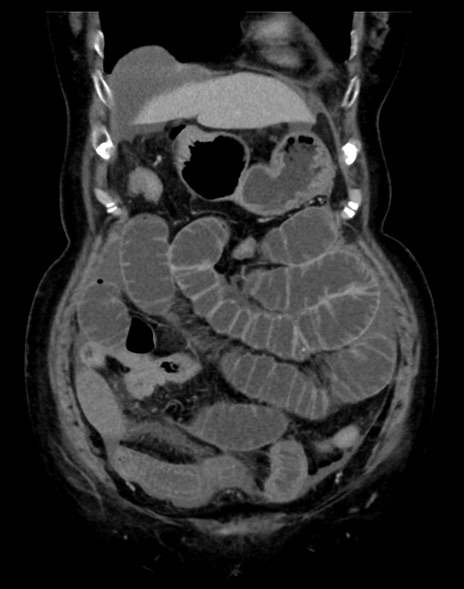

症例13 CT(冠状断像)1日半後